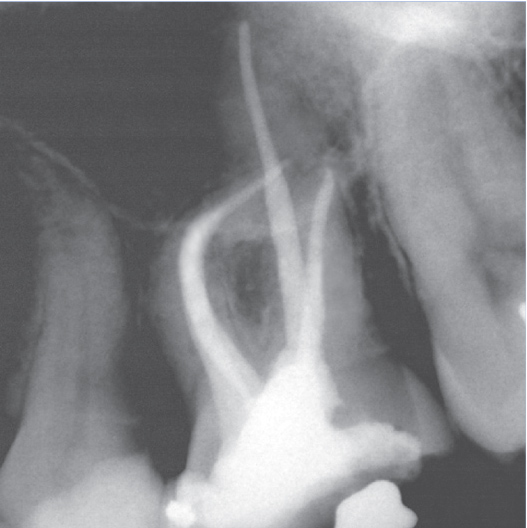

After

After Root Canal treatment